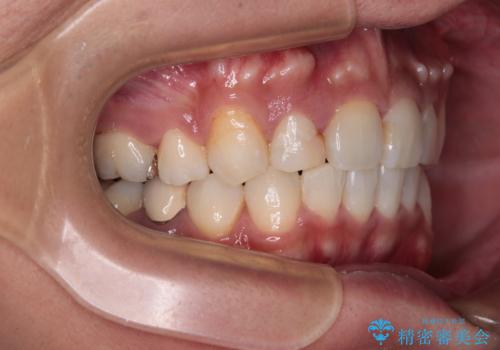

【モニター】八重歯と正中のずれた歯列 片顎抜歯のワイヤー矯正

- 上顎の八重歯と正中のズレを気にして来院された患者様です。

八重歯による叢生は著しく、それにより上顎の正中が大きく右にずれている状態でした。

口元の突出感は感じていなかったことと、奥歯の咬み合わせを考慮し、上顎のみ左右の第一小臼歯を抜歯してワイヤー装置にて矯正治療を行うこととしました。

補助装置を併用することで効率的に八重歯や正中位置の改善を達成することができました。